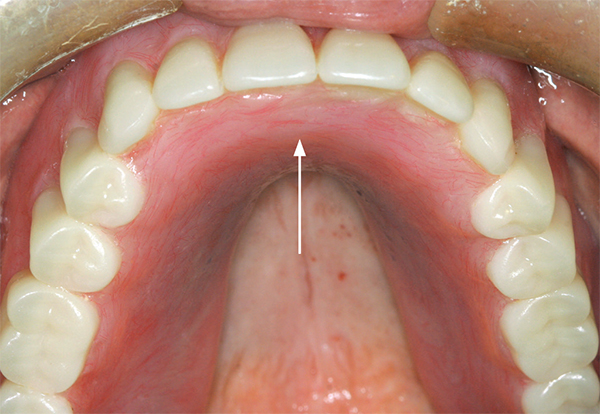

Fig 2. A periapical radiograph of an implant placed in the position of the maxillary left central incisor. The implant at mid-body was clinically confirmed to be in contact with the contents of the nasopalatine canal (arrow). This was validated by inserting a round-ended implant probe into the osteotomy before placing the implant and observing movement of the canal’s contents at the nasopalatine foramen. At the 4-year follow-up (not shown), the patient continued to be symptom free.

Figure 2

If an osteotomy is created that inadvertently results in a large perforation into the nasopalatine canal, then the contents of the canal should be removed.13 Subsequently, the implant should be inserted, and if a significant gap exists around the implant, it should be filled with bone graft material. In general, an implant should not be left in contact with soft tissue as this may interfere with osseointegration.13,14 If, however, a small mid-canal fenestration is accidentally created when preparing the osteotomy, it may go unnoticed and have little clinical effect (Figure 2).